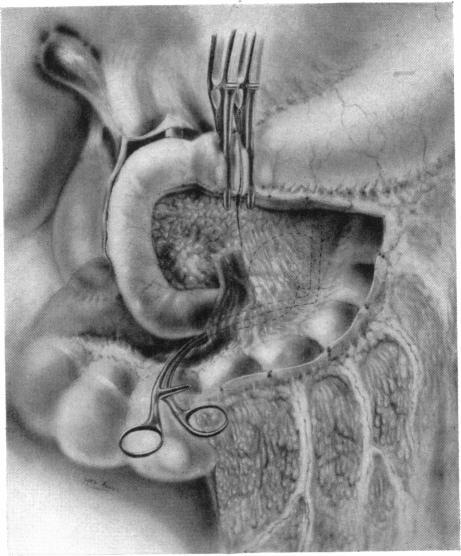

CARCINOMA OF THE PANCREAS AND AMPULLARY REGION: REPORT OF SIX ADDITIONAL CASES.

Ann Surg. 1942 Jun;115(6):1066-90. doi: 10.1097/00000658-194206000-00018.